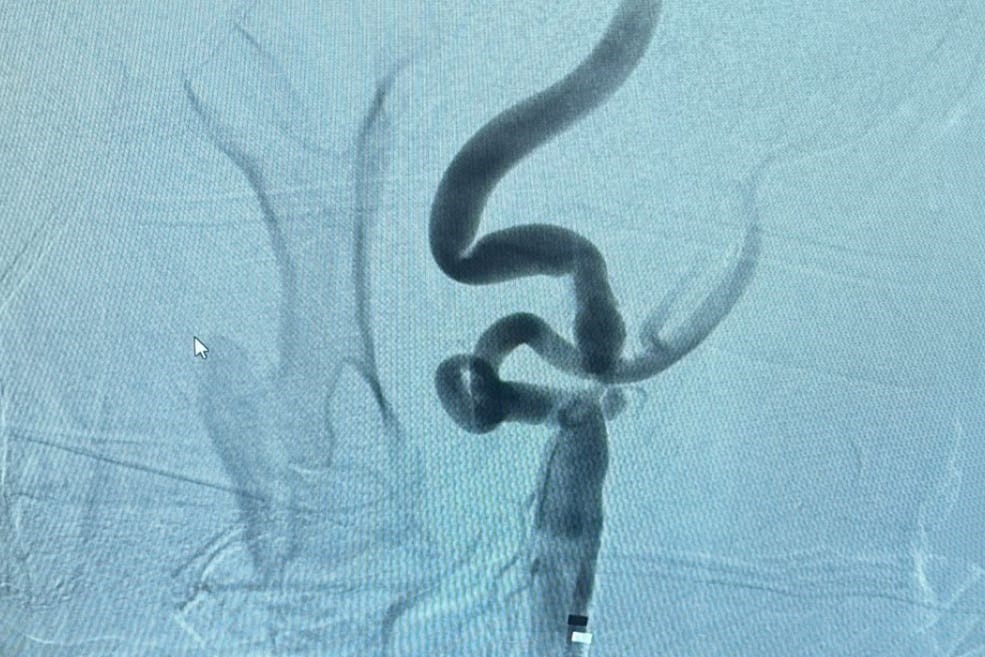

Boynun her iki yanında yer alan şah damarlarında zamanla kolesterol, kireçlenme gibi nedenlerle oluşan plaklar, damarda daralmaya neden olabiliyor. Bu durum tedavi edilmediğinde beyin felci (inme) gibi ciddi sonuçlara yol açabiliyor. Girişimsel Radyoloji Ünitesi’nde uygulanan yöntemde, darlık tespit edilen damara özel bir balon yardımıyla müdahale ediliyor ve ardından stent adı verilen ince metal bir kafes yerleştirilerek damarın açık kalması sağlanıyor. Bu sayede, kan akışı normale dönüyor ve felç riski önemli ölçüde azaltılıyor.

Anjiyografi ünitesinde, ameliyatsız olarak uygulanan bu işlem sayesinde hastalar kısa sürede iyileşme gösteriyor. Şu ana kadar tedavi edilen hastalarda olumlu sonuçlar alınırken, bu uygulama rutin bir işlem haline gelmiş durumda.